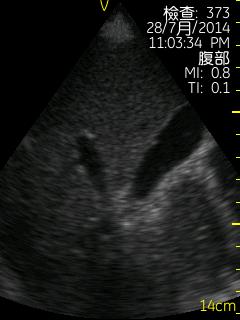

Vscan临床图片 腹部